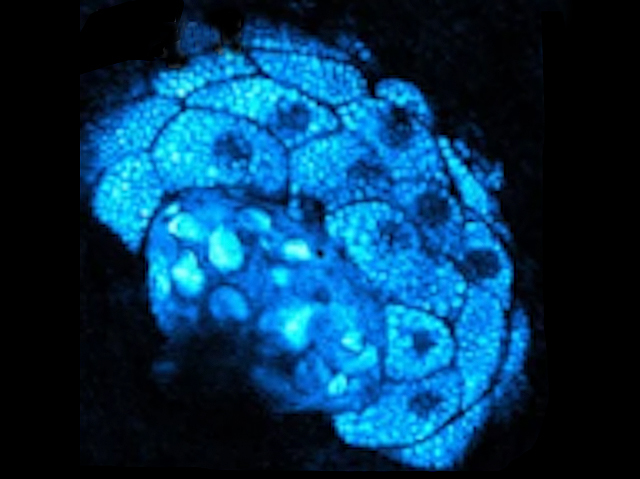

In Your Stride

We all know that sugar can give us a burst of energy. But glucose – sugar in its basic molecular form – also sustains all the molecular, cellular, and whole-body processes that keep us going. How the body is making use of glucose is an important indicator of health, so researchers are interested in tracking this progress. However, current tools for observing glucose’s journey are limited to the first steps of its metabolism, meaning it’s hard to see what happens next. A new technique called STRIDE can image the full picture of glucose uptake and metabolism, even after it is broken down into component parts and being used by cells after six days (seen here in blue, permeated through a slice of mouse tissue). Imaging glucose metabolism could ultimately help give a clear view of how diseased organs are behaving, and help develop our understanding of the way cancers power their deadly development.